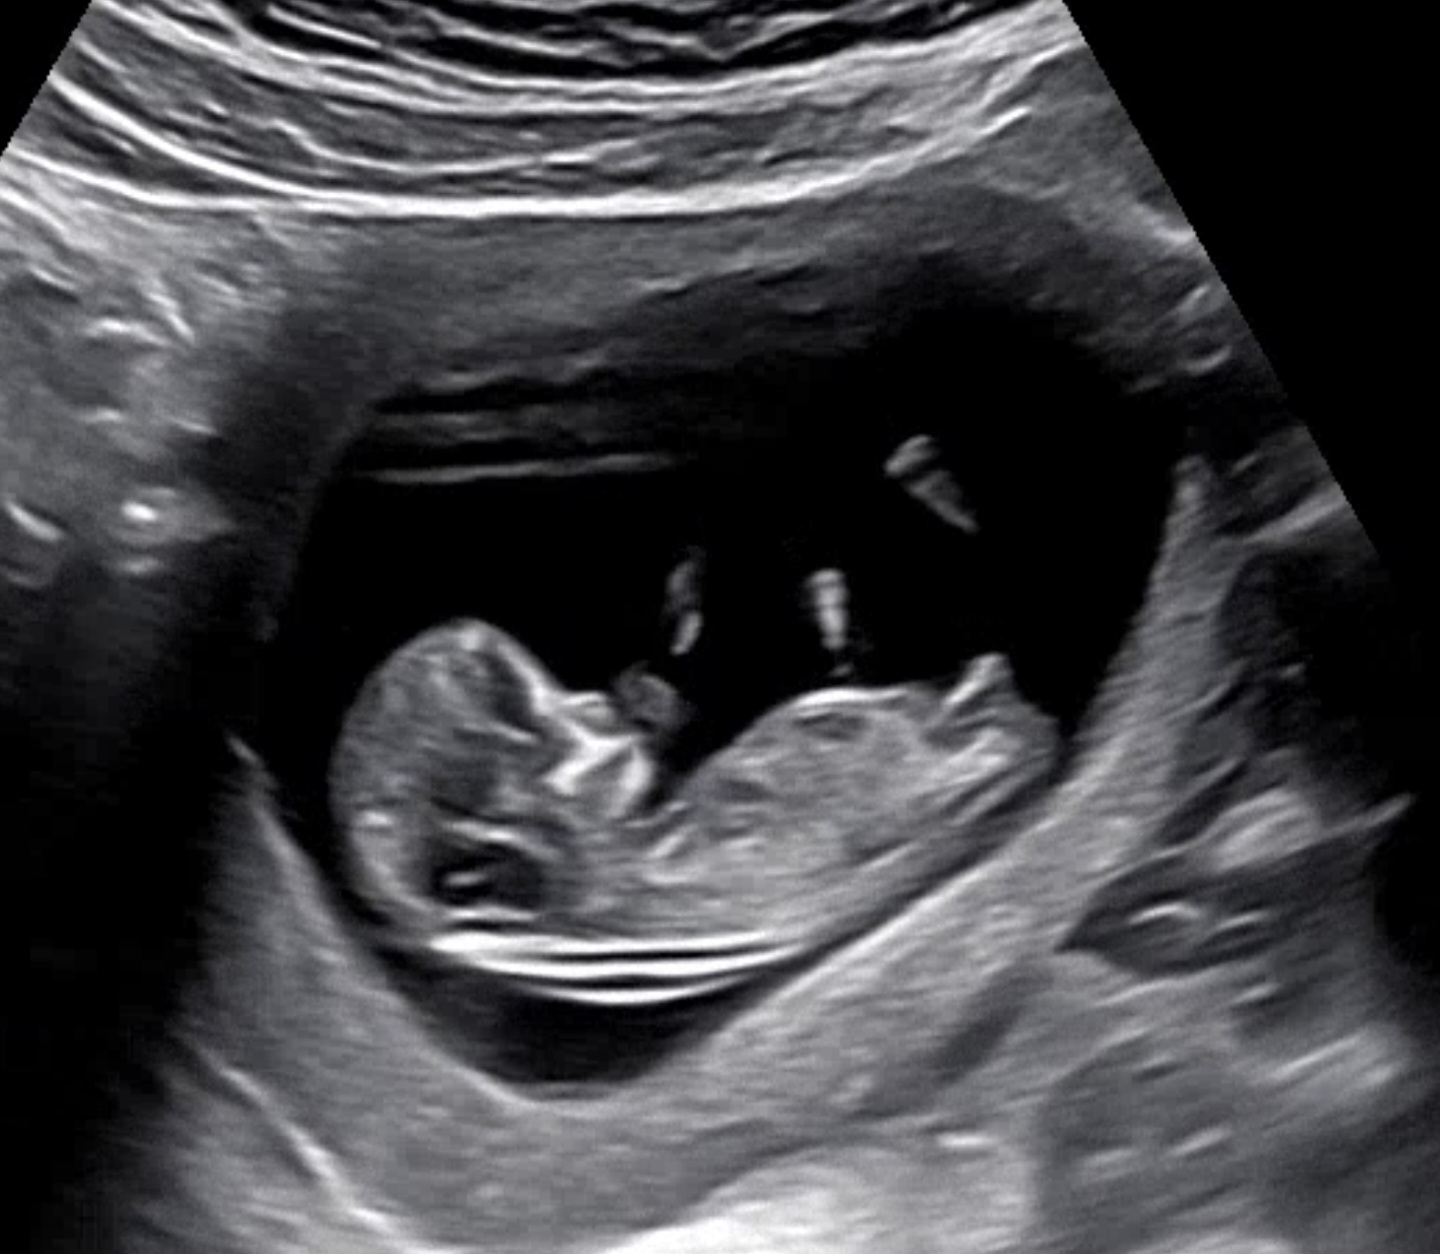

딸일까요? 아들일까요?

선배님들의 답변이 궁금해요

딸같아유

딸같아용ㅋㅋㅋ